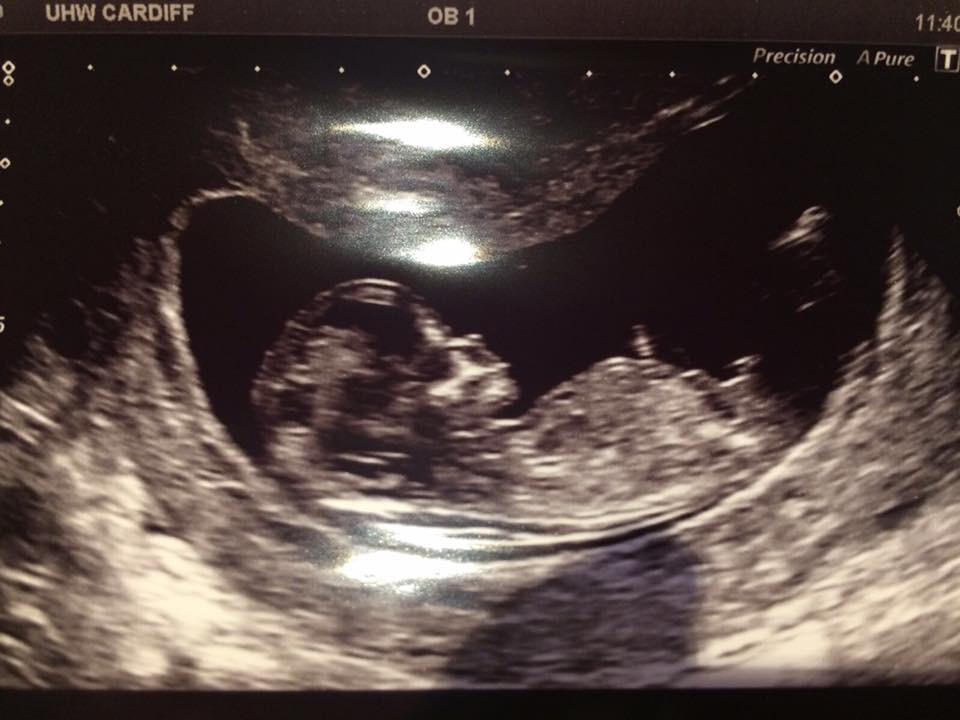

Can you please let me know if you think boy or girl?Attachment 35377Attachment 35379Attachment 35380

I thought the nub looked horizontal to the spine as baby is curved. Was thinking girl but everyone else thinks boy so guess I'm missing something xx

Definite boy, it's all about the stacking!x

Definitely boy! It's the bump above the nub = boy for sure!

The nub is short, angled upward, with stacking above the nub. This is a very classic boy nub. Congrats [emoji170]!